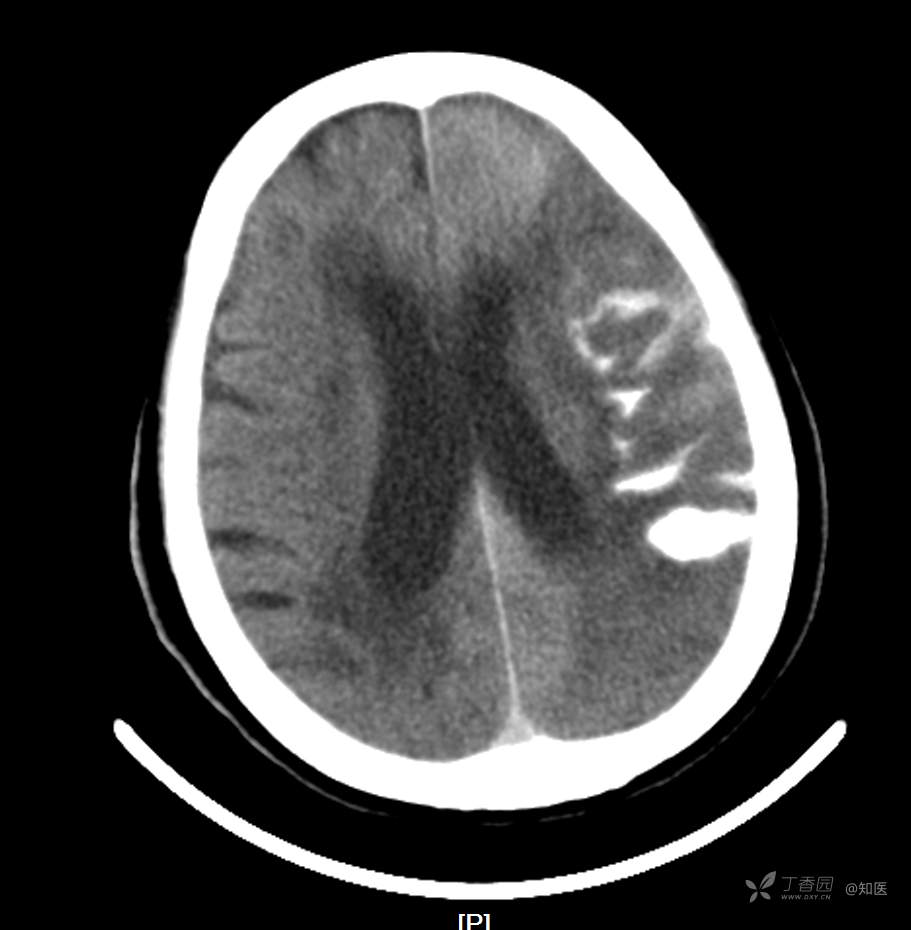

4-22日查房患者呈昏睡状,混合性失语,右侧肢体肌力障碍较入院时加重,胃肠减压引流物为深黄绿色液体,量约150ml。查体:GCS 9分(睁眼反应 3分+语言 1分+运动 5分),NHISS评分23分(意识水平 2分+提问 2分+指令 1分+凝视 2分+面瘫2+左上肢 1分+右上肢4分+左下肢 2分+右下肢4分+语言 3分),昏睡状,查体欠合作,混合性失语,粗测智能查体不配合。双眼闭目紧,双侧球结膜水肿,双侧瞳孔等大等圆,直径约4.0mm,对光反射灵敏,眼球无自主运动,无眼震,右侧鼻唇沟浅,口角向左歪斜。咽部查体不配合。转颈、耸肩查体不配合。伸舌不配合。右上肢肌力1级,右下肢肌力2级,左上肢肌力3级,左下肢肌力4级,四肢肌张力减低。四肢深浅感觉及共济运动查体不配合。右侧巴氏征阳性,左侧巴氏征阴性。颈抵抗。双侧布氏征及克氏征均阴性。辅助检查:头颅+胸部CT:与前片(2021-4-21 13:57)对比,现片示:1、环池、桥前池及大脑镰后部及小脑幕高密度影,考虑出血,较前新发。2、额颞顶叶高低混杂密度影,考虑梗塞伴造影剂残留;左侧大脑中动脉走行区致密影,系术后改变;请结合临床。3、多发腔梗,脑白质脱髓鞘,脑萎缩。4、双肺间质性改变,双肺下叶纤维索条,双侧胸腔微少量积液征象,双侧胸膜增厚。5、主动脉及冠状动脉管壁多发钙化斑块。三线主任医师、二线主治医师查房后示:根据患者病史、体征及辅助检查,目前诊断:1.脑梗死出血转化;2.左侧大脑中动脉次全闭塞;3.左侧大脑中动脉支架植入术后;4.高血压2级(很高危);5.2型糖尿病;6.应激性溃疡伴出血。目前病情及治疗上需注意以下问题:1.患者出血转化,增加脱水剂剂量,调整为20%甘露醇 125ml 每8小时一次、甘油果糖 250ml 每12小时一次,同时结合患者球结膜水肿,白蛋白正常低值,今日给予补充人血白蛋白10g,注意监测电解质等变化。2.患者为蛛网膜下腔出血,给予泵入尼莫地平预防脑血管痉挛。3.患者左侧大脑半球见大片脑白质脱髓鞘,考虑脑白质营养不良,给予维生素B1、维生素B12、维生素C、维生素B6及依达拉奉改善微血管通透性;4.患者出现应激性溃疡伴出血,今日暂禁食,给予泮托拉唑抑酸及肠外营养补充,密切观察消化道出血情况,根据病情变化调整抑酸药物剂量及频次;5.患者卧床,今晨见明显痰多,给予化痰等对症处理,监测血常规及脓毒症2项指标。6.向家属再次告知病情,因患者高龄、既往高血压及糖尿病病史,此次治疗出现出血转化,存在意识障碍加深、病情加重可能。7.密切观察神经系统体征变化。遵嘱执行。